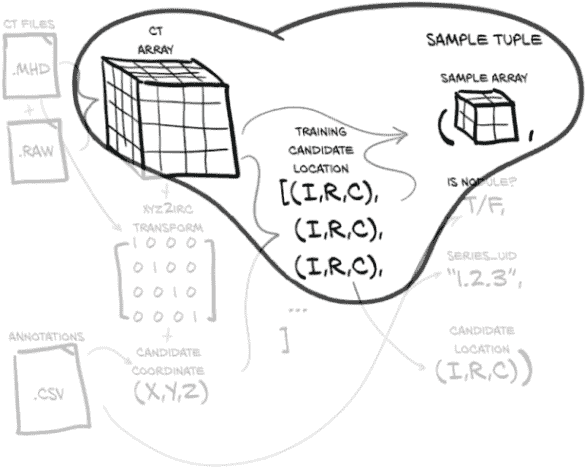

我们的目标是能够根据我们的原始 CT 扫描数据和这些 CT 的注释列表生成一个训练样本。这听起来可能很简单,但在我们加载、处理和提取我们感兴趣的数据之前,需要发生很多事情。图 10.2 展示了我们需要做的工作,将我们的原始数据转换为训练样本。幸运的是,在上一章中,我们已经对我们的数据有了一些理解,但在这方面我们还有更多工作要做。

图 10.2 制作样本元组所需的数据转换。这些样本元组将作为我们模型训练例程的输入。

我们的Ct类将消耗这两个文件并生成 3D 数组,以及转换矩阵,将患者坐标系(我们将在第 10.6 节中更详细地讨论)转换为数组所需的索引、行、列坐标(这些坐标在图中显示为(I,R,C),在代码中用_irc变量后缀表示)。现在不要为所有这些细节担心;只需记住,在我们应用这些坐标到我们的 CT 数据之前,我们需要进行一些坐标系转换。我们将根据需要探讨细节。

我们还将加载 LUNA 提供的注释数据,这将为我们提供一个结节坐标列表,每个坐标都有一个恶性标志,以及相关 CT 扫描的系列 UID。通过将结节坐标与坐标系转换信息结合起来,我们得到了我们结节中心的体素的索引、行和列。

使用(I,R,C)坐标,我们可以裁剪我们的 CT 数据的一个小的 3D 切片作为我们模型的输入。除了这个 3D 样本数组,我们必须构建我们的训练样本元组的其余部分,其中将包括样本数组、结节状态标志、系列 UID 以及该样本在结节候选 CT 列表中的索引。这个样本元组正是 PyTorch 从我们的Dataset子类中期望的,并代表了我们从原始原始数据到 PyTorch 张量的标准结构的桥梁的最后部分。